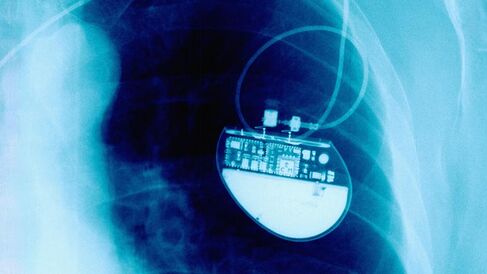

Implantable electronic medical devices are already widely used for a number of applications, but they also offer the prospect of transforming the treatment of intractable conditions, such as the use of neural electrical stimulators for spinal injury patients.

There is one major problem, however: our body recognises, attacks and surrounds these implants with a dense, ‘protective’ capsule of scar tissue that prevents electrical stimulation reaching the nervous system.